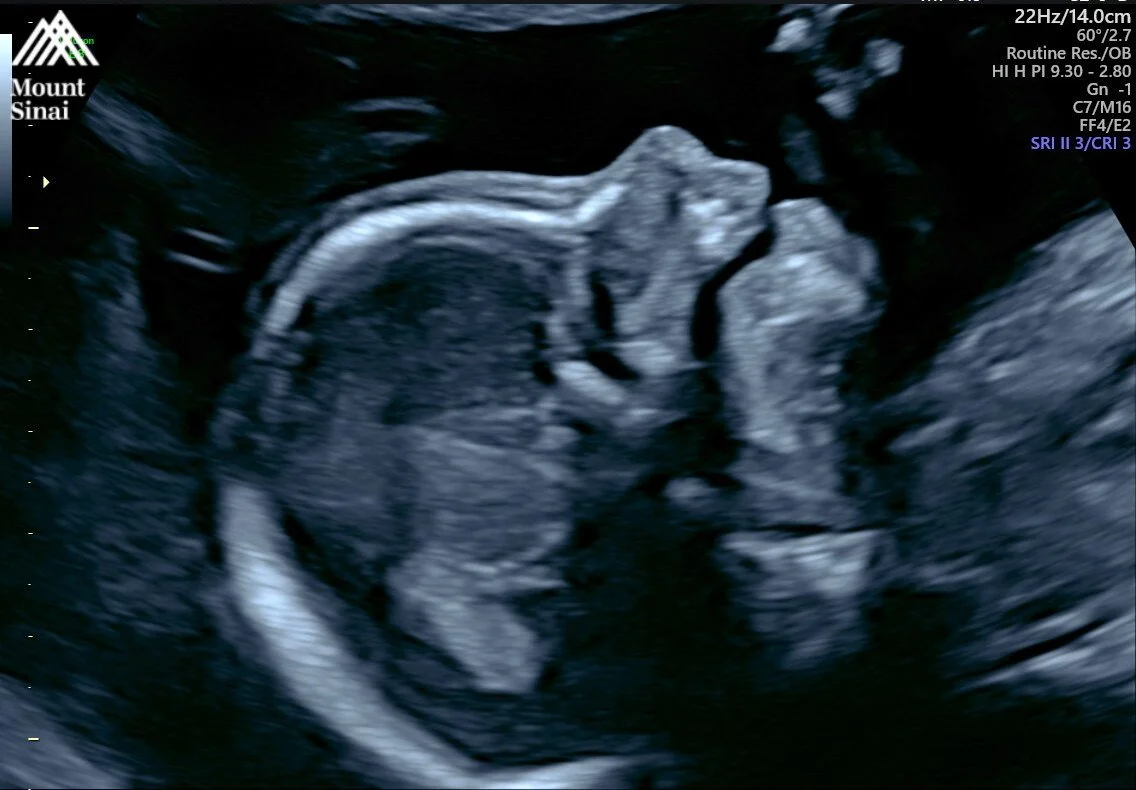

I had my 20-week anatomy scan, and baby girl is growing perfectly.